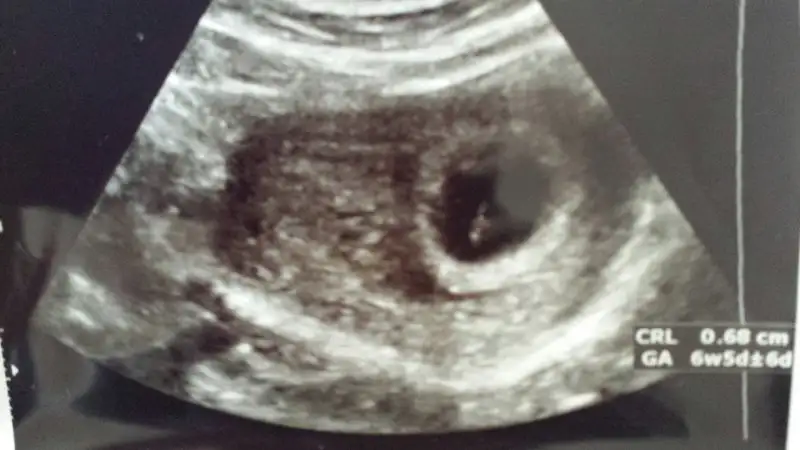

Plesenta sağda kız ama kesenin içindeki bebeğin konumunu pek anlayamadımbu usg de yorumlayabilir misiniz?

canım ilginc olanı bu usg aldıktan sonra ertesi gün başka bir doktora gittim ve kese çok farklıydı bak gönderiyorum. bir gün aralıkla farklı usg resimleri bir kız bir erkek mi olacak yaniPlesenta sağda kız ama kesenin içindeki bebeğin konumunu pek anlayamadım

Aaa evet burada erkek gibi plesentanın konumu Bebek erkek gibi burada ama ortada hiç belli olmazcanım ilginc olanı bu usg aldıktan sonra ertesi gün başka bir doktora gittim ve kese çok farklıydı bak gönderiyorum. bir gün aralıkla farklı usg resimleri bir kız bir erkek mi olacak yani

benimde kafam senin ki gibi karışık...yani ekranda gördügün gibi cıkmadı usg de dimi yani benim tek inandıgım doktor karnının hangi tarafından baktı? benim solumdan baktı ama usg resimi karnıma tutunca sagımda kalıyor:-/ keşke sana yardımcı olabilsem ama bende anlamıyorumkivilcim82 canım ben geçen hafta yani 6 hafta bitiminde ultrasona girdim karşımdaki ekranda bebeği sağa yapışık gördümm fakat doktor bana usg kağıdını verirken o noktayı büyütüp vermiş bu nedenle kağıtta hiç belli değil... Ben de heyecanlanıyodum alıcam burada paylaşıcam diye ama anlaşılır değil yani...